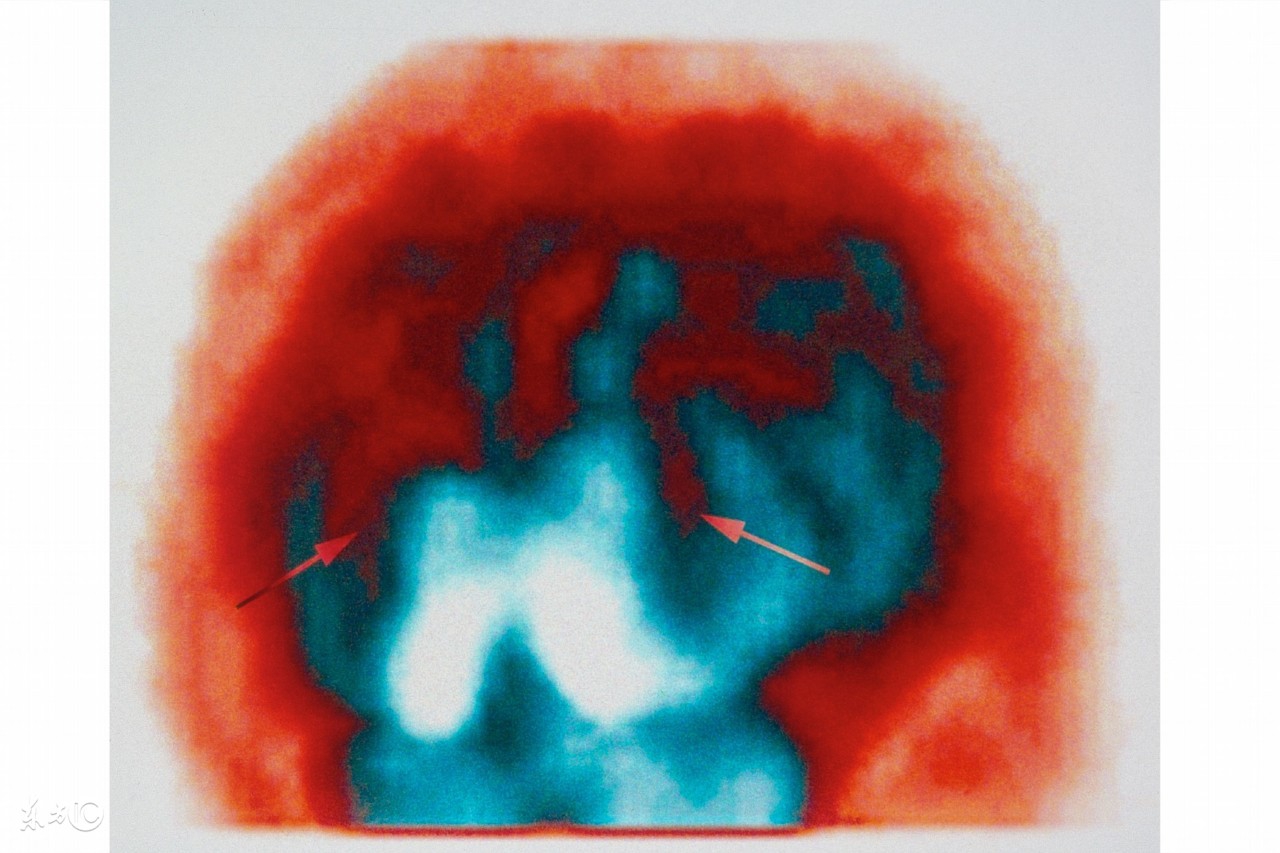

新生儿缺血缺氧性脑病主要见于有严重窒息的足月新生儿,均有明显的宫内窘迫史。由于宫内缺血缺氧影响胎儿脑细胞的能量供给。脑的能量来源和其他器官不同,几乎全部由葡萄糖氧化而来。新生儿脑的代谢最旺盛,脑的能量占全身氧能量的一半,但脑内糖原很少,而葡萄糖及氧全靠血液供给,故缺血缺氧首先影响脑的代谢。